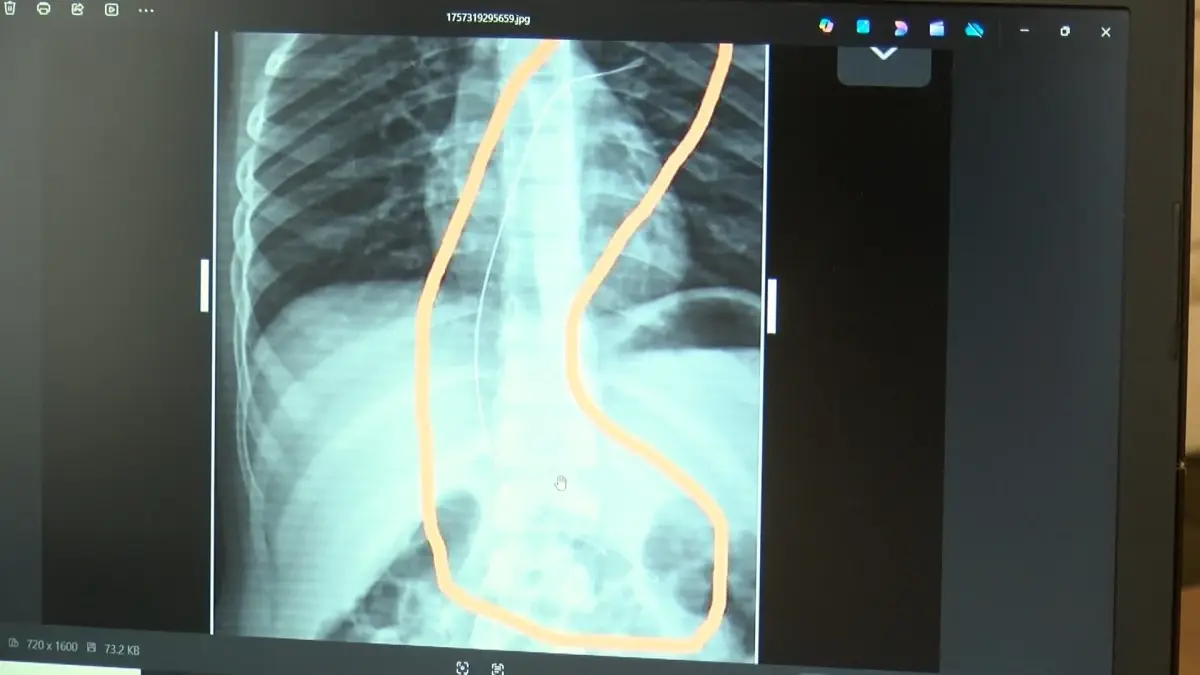

Şırnak’ta yaşayan Semra (37) ve Mehmet Ötün (40) çiftinin oğulları Aram Devran Ötün, mayıs ayında piknikteyken salatalık parçası yuttuktan sonra öksürük ve kusma şikayetleri görülünce Şırnak Devlet Hastanesi’ne götürüldü. Burada çekilen röntgen ve MR’da Aram’ın vücudunda kateter unutulduğu görüldü. Diyarbakır’daki Gazi Yaşargil Eğitim ve Araştırma Hastanesi Kadın Doğum ve Çocuk Ek Binası’na sevk edilen Aram, 5,5 saat süren riskli bir ameliyata alınarak 18 santimetre uzunluğundaki kateter çıkarıldı. Ameliyat sonrası yapılan incelemelerde kateterin kalp kapakçığına ve ciğerlerine zarar verdiği belirlendi.

Ailenin avukatı Ahmet Yalçın, hastane hakkında hem şikayetçi olduklarını hem de dava açtıklarını belirterek, “Müvekkilim Aram Devran Ötün, 2022 Eylül ayında Dicle Üniversitesi Hastanesi’nde Stevens- Johnson hastalığı nedeniyle tedavi gördü. Tedavi sırasında kendisine kateter takıldı. 18 santimetre uzunluğundadır. Bunu takarken büyük bir ihmalkarlık yapılarak vücudunda unutuldu. Mayıs ayında müvekkilim çok öksürdüğü için Şırnak Devlet Hastanesi’ne kaldırıldı. Burada yapılan tetkiklerde kateterin unutulduğu tespit edildi. Daha sonra Diyarbakır Gazi Yaşargil Kadın ve Çocuk Hastalıkları Hastanesi’ne götürüldü. Çok riskli bir ameliyata alındı ve kateter çıkarıldı. Bu kateterin vücutta yol aldığı tespit edildi. İlk giriş yeri ve çıkarıldığı yer arasında çok fark var ve kalp kapakçığı ile ciğerlerine zarar verdiği tespit edildi. Müvekkillerimin hem maddi hem de manevi zararlarını karşılamak adına Dicle Üniversitesi’ne biz başvuruda bulunduk. 30 günlük cevap süresi içerisinde bize geri dönüş yapılmadı. Biz de maddi ve manevi zararların tazminat için Diyarbakır İdare Mahkemesi’ne davamızı açtık ve sorumlulardan şikayetçi olduk” dedi.

Oğlunun piknikte salatalık parçası yuttuktan sonra sürekli öksürmeye ve kusmaya başladığını söyleyen Semra Ötün, “Çocuğum 3 yıl önce Steven Johnson sendromu hastalığına yakalandı. Milyonda bir görülen antibiyotikten kaynaklı bir hastalık. Doktorlar öyle söyledi. Bizi acilen Diyarbakır Dicle Üniversitesi Çocuk Hastanesi bölümüne sevk ettiler. 1 ay yoğun bakım sürecimiz oldu. 28 gün yoğun bakımda, 3 günde serviste kaldı. Damar yolundan, kasıktan serum taktılar. Kateter denilen tel çocuğun vücudunda bırakılıyor. Biz taburcu olduğumuzda fark edilmiyor. 3 yılın sonunda biz bunu fark ettik. Pikniğe gittik. Oğlum salatalık parçası yuttu ve salatalık parçasından sonra akşama kadar öksürdü. Hiçbir şekilde durmadı. Kusuyordu. Ben şüphelenmeye başladım. Çocuğum normal değildi. Sonra eşime danıştım. Akşam 21.00 civarında acile götürdük. Röntgeni ve MR’ı çekildi. Tuhaf bir şey olduğunu anladık. Doktor röntgeni gösterdi. Tel kalmıştı. Çok kötü bir şekilde. Acil doktoru film çektikten sonra bize bir tel parçasını gösterdi. Bizi bekletmeden Diyarbakır’a sevkimizi verdiler. Diyarbakır Gazi Yaşargil Eğitim ve Araştırma Hastanesi Kadın Doğum ve Çocuk Ek Binası’na gittik. Çocuğun kasıklarından anjiyo yolu ile teli çıkaracaklarını ama riskli bir ameliyat olduğunu söylediler. O süreçte çocuk gerçekten sürekli yoruluyordu. İkide bir oturuyordu. ‘Anne çok yoruldum, karnım ağrıyor’ diyordu. Ben ağrı kesiciler ile geçiştirmeye çalışıyordum. Bu telin 3 yıl boyunca çocuğumda kaldığını öğrendim. Ailece yıkıldık” diye konuştu.